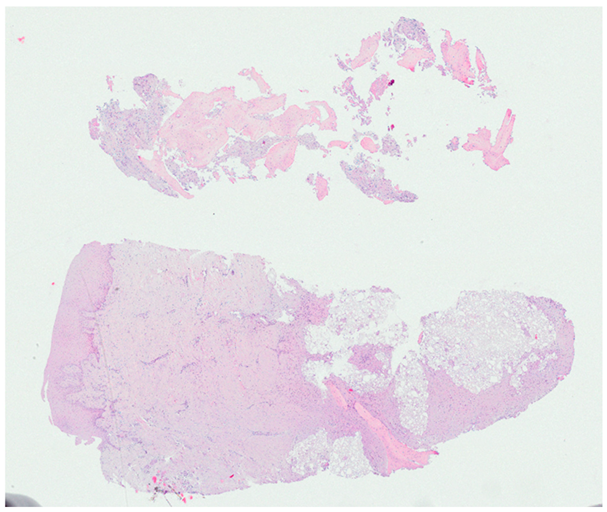

3.2. Histological Observation